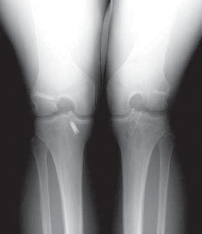

3. Routine radiographs, including weight-bearing anteroposterior and lateral views as well as patellar views, should be performed. In the revision setting, these images allow for critical assesment of previous tunnel placement and assesment for possible bone loss at previous tunnels, which may require further evaluation and treatment.

1. Metallic fixation devices make previous tunnel placement easy to identify, but bioabsorbable screws and other types of fixation also can be evaluated for tunnel placement on these images (

FIG 1

).

FIG 1 • A,B. Anterior cruciate ligament (ACL) reconstruction performed with an EndoButton (Smith & Nephew, Andover, MA) on the femur and staple fixation of the graft on the tibia. C,D. Anterior placement of the femoral tunnel in this primary ACL reconstruction performed with a two-incision technique. A B C

D

13. A common cause of failure related to surgical technique is anterior placement of a femoral tunnel, which often is detected on the lateral radiograph (

FIG 1D

).6,10 This may lead to tightening of the graft with knee flexion resulting in graft stretch-out or failure.